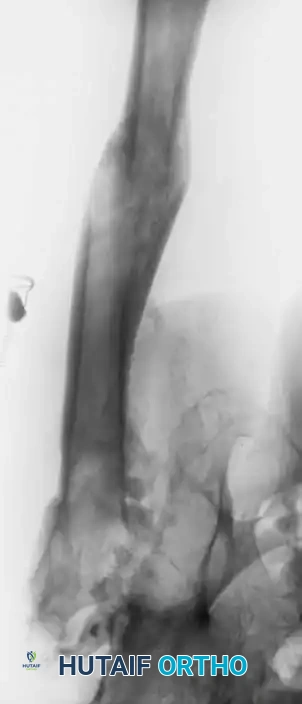

If surgery is undertaken, an extensile exposure is required. The ectopic bone severely distorts and obscures normal anatomic landmarks, placing the sciatic nerve and femoral vessels at high risk. The abnormal bone does not easily "shell out" of the surrounding soft tissues, and substantial intraoperative blood loss should be anticipated. Excision should be delayed until the bone is fully mature (typically 12 to 18 months postoperatively), confirmed by a normalizing alkaline phosphatase level and cold bone scan. Postoperative prophylaxis with radiation or NSAIDs is mandatory to prevent recurrence. While range of motion reliably improves following excision, patients must be counseled that pain may not be completely alleviated.